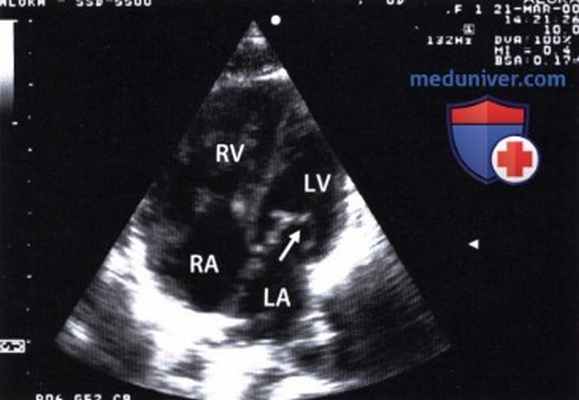

Тяжелая форма врожденного митрального стеноза, выявленная при двумерной ЭхоКГ из апикальной четырехкамерной позиции. Отчетливо видно выпячивание створок митрального клапана в левый желудочек (стрелка). Открытие митрального клапана видно нечетко. В отличие от митрального клапана, трехстворчатый клапан (слева) открывается нормально, о чем свидетельствует параллельное расположение створок. Тем не менее левое предсердие не увеличено, что объясняется незаращением овального окна, через которое происходит сброс крови слева направо.

в) Двумерная эхокардиография. Подвижность створок митрального клапана при диастолическом открытии ограничена, что наиболее отчетливо видно при сканировании из апикальной четырехкамерной позиции, при которой отмечается недостаточная диастолическая сепарация свободного края передней и задней створок. Обе створки выдаются в левый желудочек.